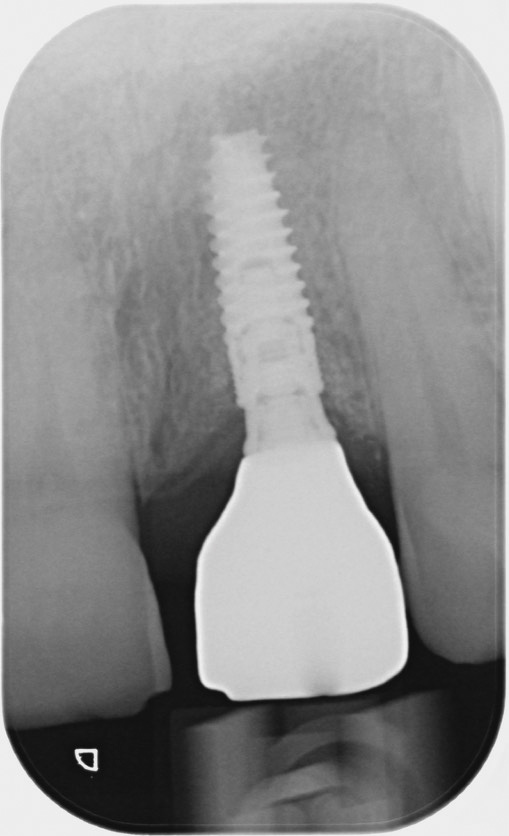

Al controllo a 12 mesi la situazione appare stabile e al controllo radiografico si apprezza il mantenimento dei livelli ossei peri-implantari (fig.19,20).